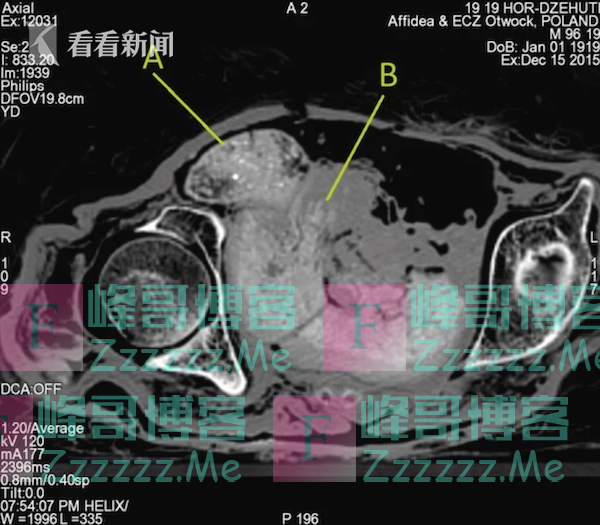

在此之前,埃及开罗大学的放射科医生萨哈尔·萨利姆曾对胎儿的发现表示质疑,她指出在对木乃伊的扫描中并未发现胎儿的骨骼。研究小组认为,胎儿骨骼由于木乃伊体内的酸化过程而脱矿。另外,在尸体的分解过程中,尸体内部发生的酸化过程会进一步导致已非常脆弱的胎儿骨骼进一步脱矿。研究人员表示,“在酸性环境中骨骼脱矿的过程可以与鸡蛋实验相类比,想象一下把一个鸡蛋放进装满酸的锅里。蛋壳会溶解于酸,只留下里面的东西(蛋白和蛋黄)。”